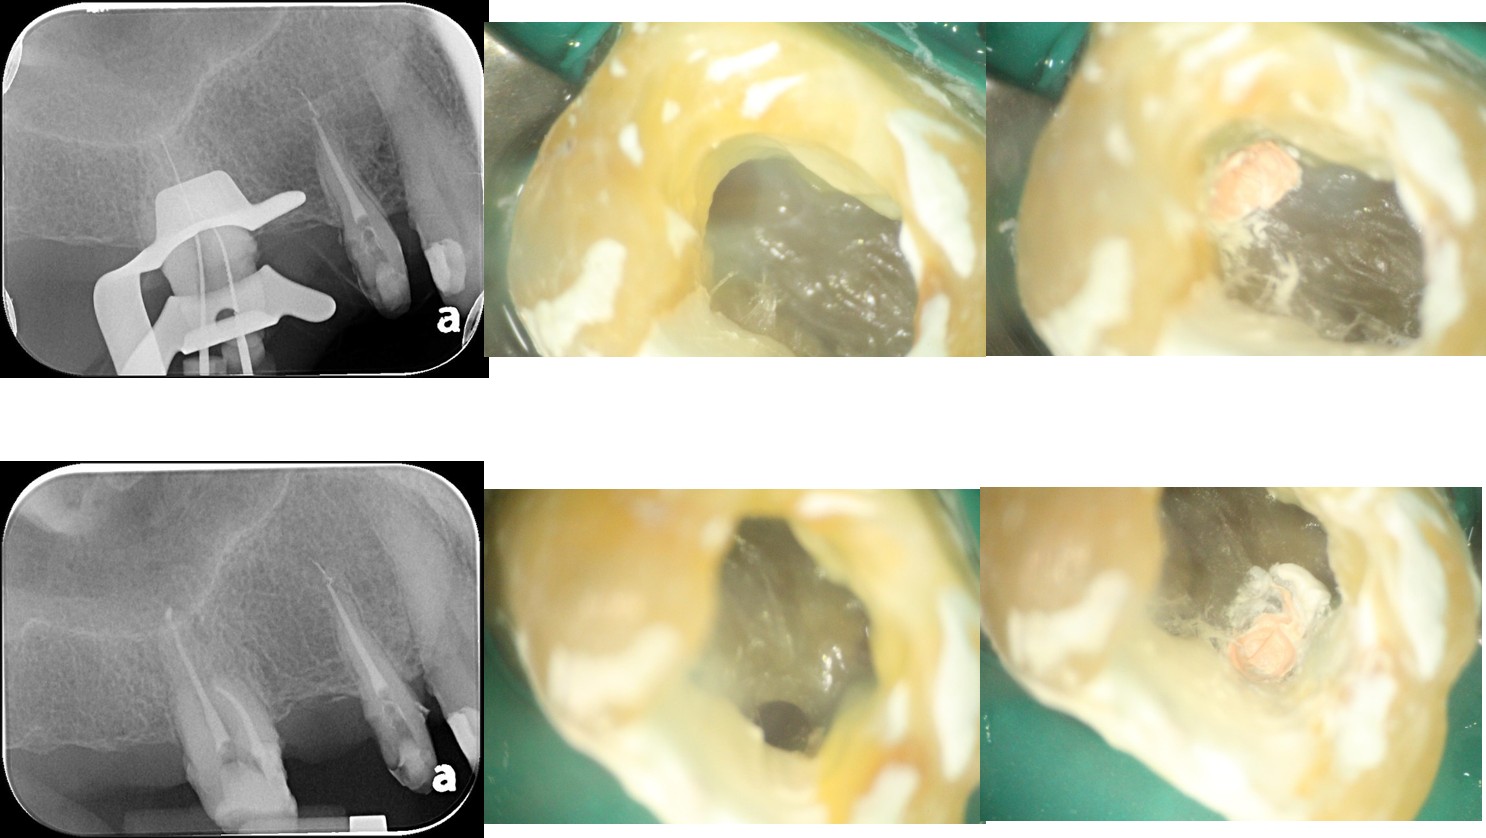

大臼齒顯微根管治療

鑄造金屬釘柱